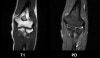

1. Coronal section

1) Collateral ligament

2) Common extensor/flexor tendon group patholgy as well as epicondylitis